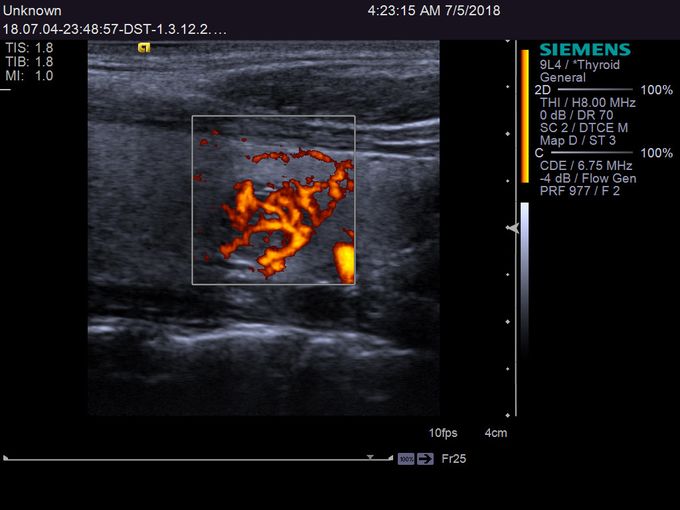

Кроме новой техники, можно заказать восстановленные медицинские системы: ультразвуковые сканеры, томографы, флюороскопы, ангиографы и хирургические установки С-дуга.